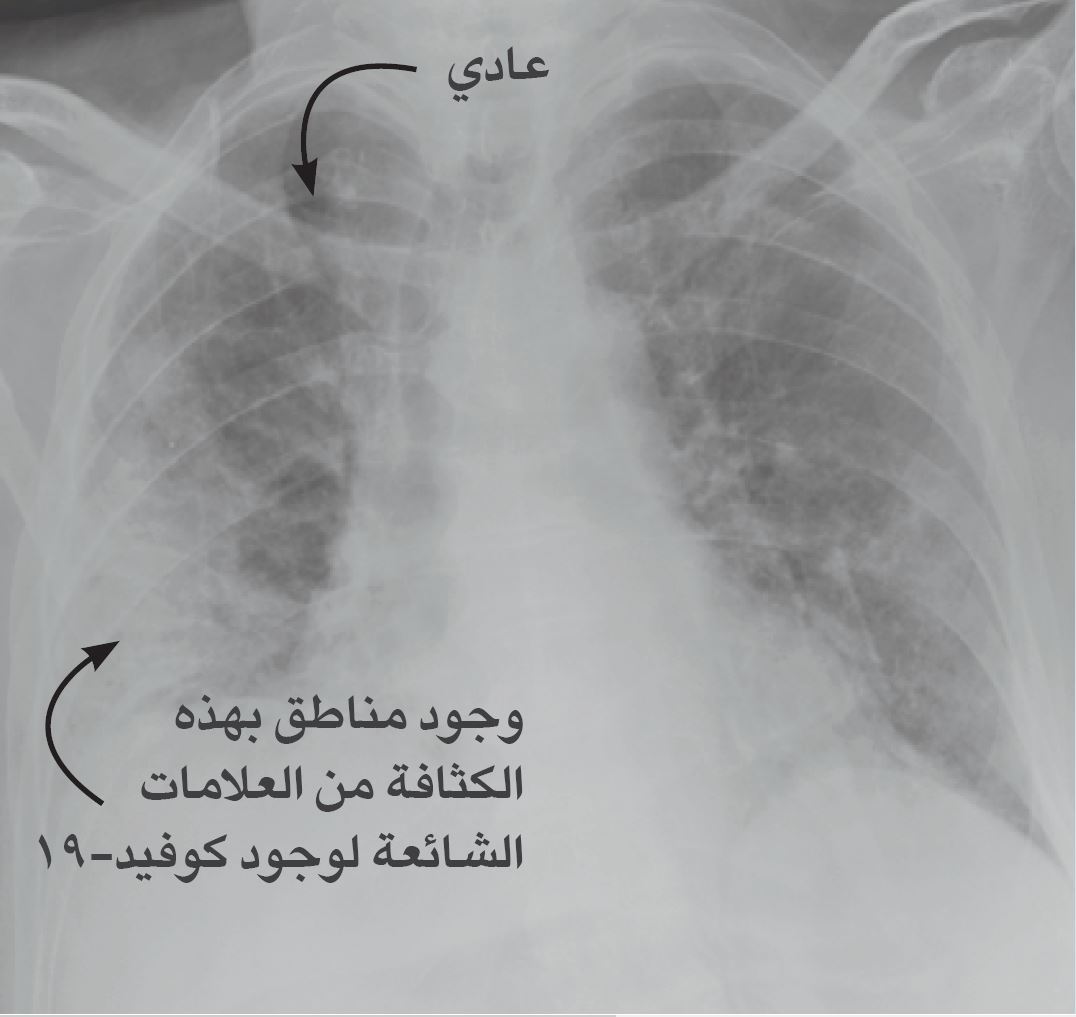

???? ??????? ??????? ????? ??????? ???? ???? ??????? ??????-?? ???? ??????? ???? ??????? ?? ???? ????? ??????

(?????? ??: ??. ?????/???? ???? ??????? ?????? ???? ???????-??????? ?????? ????? ?????? ????? ???????)